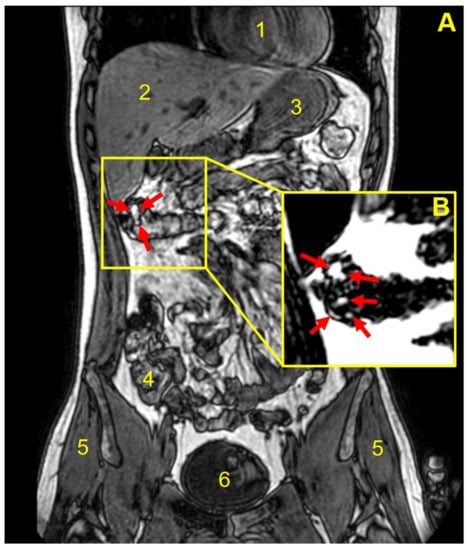

| Participant | Weight Gain (mg) a | Weight Gain Per Surface Area (mg/mm2) | Gastrointestinal Location and Integrity of the Capsule at the Different Imaging Time Points (min) | |||||||

|---|---|---|---|---|---|---|---|---|---|---|

| 45 | 90 | 135 | 180 | 225 | 270 | 315 | 360 | |||

| 1 | 9.2 ± 0.8 | 0.02 | Stomach | Stomach | Stomach b | NO c | NO | NO | NO | NO |

| 2 | 18.2 ± 1.2 | 0.04 | Stomach | Stomach | Duodenum | Duodenum | Term ileum | NO | NO | d |

| 3 | 18.2 ± 1.2 | 0.04 | Stomach | Stomach | Term ileum | Asc colon | Hep flexure | Hep flexure | Hep flexure | Hep flexure |

| 4 | 18.2 ± 1.2 | 0.04 | Stomach | Jejunum | Jejunum | Jejunum | Term ileum | Term ileum | Term ileum | NO |

| 5 | 18.2 ± 1.2 | 0.04 | Stomach | Jejunum | Cecum | Cecum | Asc colon | Asc colon | NO | Hep flexure |

| 6 | 18.2 ± 1.2 | 0.04 | Stomach | Stomach | Term ileum | Term ileum | NO | NO | NO | NO |

| 7 | 18.2 ± 1.2 | 0.04 | Stomach | Jejunum | Jejunum | Term ileum | Term ileum | NO | NO | NO |

| 8 | 36.0 ± 5.2 | 0.08 | Stomach | Jejunum | Term ileum | Cecum | NO | NO | shade | |

| 9 | 52.6 ± 9.7 | 0.11 | Stomach | Duodenum | Term ileum | Hep flexure | Hep flexure | Trans colon | Trans colon | |

| 10 | 52.6 ± 9.7 | 0.11 | Stomach | Stomach | Duodenum | Duodenum | NO | NO | ||